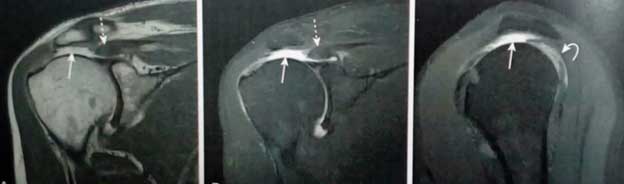

چون پارگی روتاتور کاف معمولا بعد از ضربه به شانه اتفاق می افتد، تشخیص این بیماری معمولا با تاخیر صورت می گیرد. پارگی می تواند کوچک یا کامل باشد و تصویر کلینیکی را مبهم کند. اما با استفاده از معاینه فیزیکی دقیق و با کمک از MRI و تصویربرداری سونوگرافی می توان وجود یا عدم وجود این بیماری را اثبات کرد.

تصویر MRI: